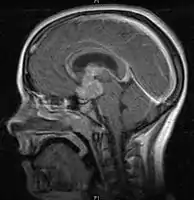

- Mainly located in midline structures, suprasellar region or pineal gland, also basal ganglia and hypothalamus

- Pineal Gland Germinoma

- Suprasellar Germinoma